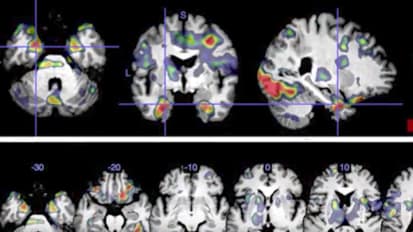

Johns Hopkins neurosurgeon Daniel Lubelski discusses the importance of pathology, biomarkers and genetics in treatment of spine tumors. Immunotherapy and targeted therapies are used to approach tumors that have been bio-banked and gene-sequenced, resulting in a tailored treatment plan. This, combined with advanced medical and surgical options, is leading to the best possible outcomes for patients with spine tumors.